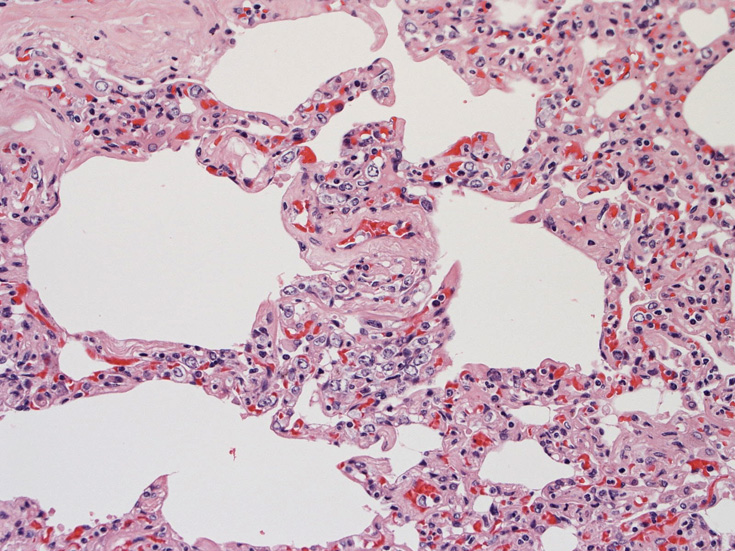

肺A;肺胞壁が厚くなり毛細血管内に腫瘍細胞が多数出現している(A).

肺組織所見